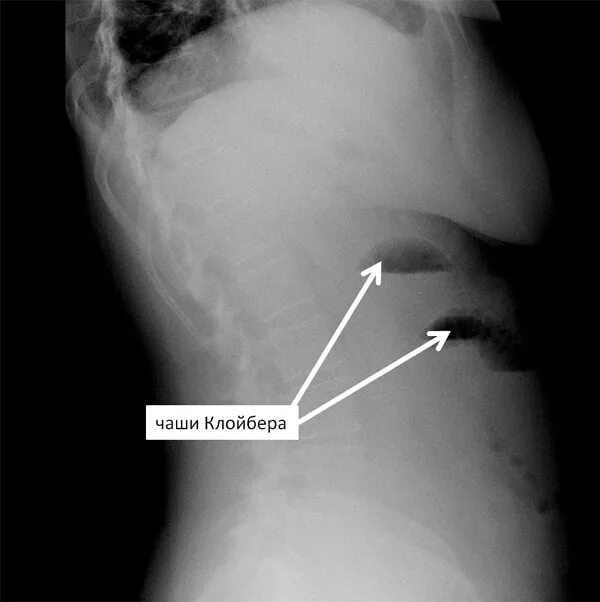

Симптом чаши